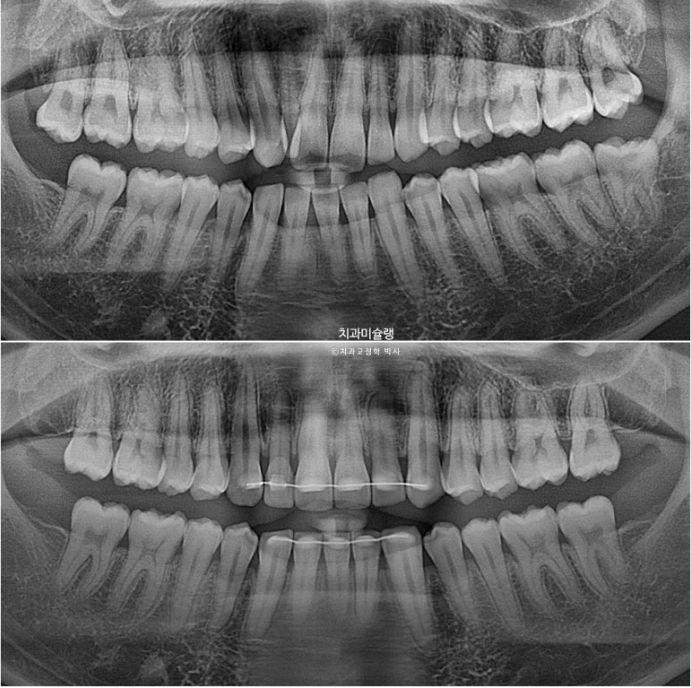

치료 전 후 파노라마 엑스레이를 보면 블랙트라이앵글의 원흉이었던 아래 앞니 치축 기울어짐이 해소된게 보입니다.

위 앞니 치축도 평행해졌습니다.

<인비절라인으로 뿌리 이동은 안된다.>는 잘못된 말입니다.

1년 8개월간의 치료 기간동안 치근흡수는 없습니다.

24.03~25.11

어금니 교합은 기존 2급에서 1급 교합관계를 달성

치근 평행도는 좋습니다.